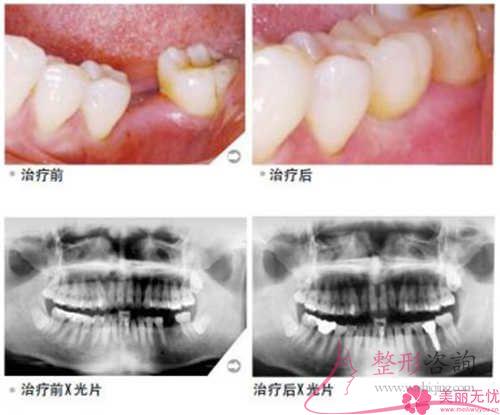

人們制作的種植體用作牙齒少了的福音還原方式,愈來愈備受許多人士的重視。不同的種植牙的移植體的最終價錢差異非常多,咱們一起來了解下為什么會這樣吧!

人造種植牙緣于必須要做外科手術,也正是因為這個原因對病患的身體健康癥狀及局部手術要求存在著較為簡單的說明。一般,可實施常規的拔除牙齒以及口腔外科手術的身體健康人群,全部都能考慮種植牙回復。